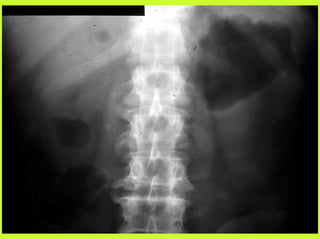

3) RADIO (PNO)

RADIOGRAPHIES

ABDOMEN SP -scanner

PNEUMOPERITOINE SUR SUJET DEBOUT

" Croissant gazeux sous diaphragmatique

" Disparition du niveau hydroaérique gastrique

PNEUMOPERITOINE SUR SUJET COUCHE

" Visibilité du ligament triangulaire du foie

" Visibilité anormale des parois intestinales

" Image aérique pré-hépatique

"Pneumatisation de MORRISSON

(cul de sac inter-hépato-rénal)

AUTRES EXAMENS

"TOGD aux hydrosolubles?

" Echo, scanner

" Coelioscopie ?

" Pas de lavement colique, pas de fibroscppie, pas de coloscopie, pas

d’IRM